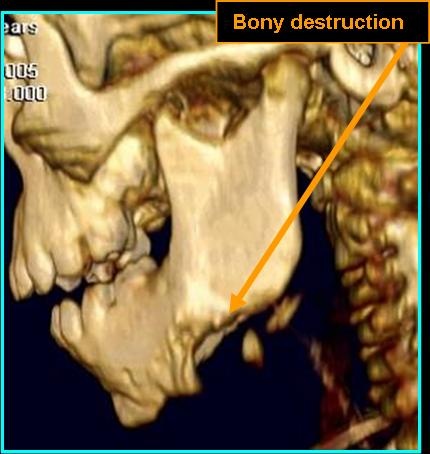

- May be well-defined or invasive - displacing and eroding surrounding bone

Radiologic Findings

- On CT: Mild to moderate enhancement with contrast, may appear malignant, has no observable tumor matrix or calcification/ossification